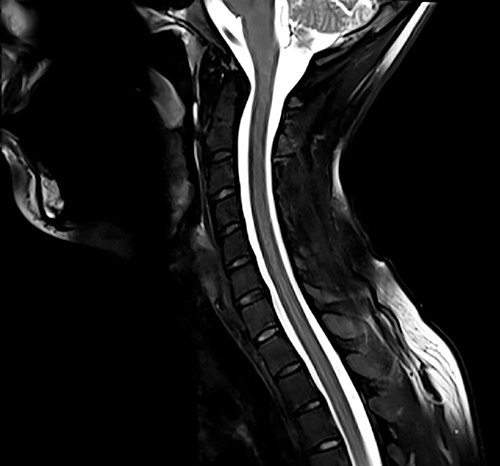

Ο Magnetom Lumina διαθέτει πολυκάναλα πηνία τελευταίας τεχνολογίας για υψηλής διαγνωστικής αξίας απεικόνιση της ανατομίας και της λειτουργίας όλων των περιοχών του ανθρωπινου σώματος. Διαθέτει δυνατότητα πραγματοποίησης όλου του φάσματος των εξετάσεων Μαγνητικής Τομογραφίας, όπως νευρολογικών, ογκολογικών, μυοσκελετικών, καρδιολογικών εξετάσεων, καθώς και ειδικές εξελιγμένες τεχνικές απεικόνισης. Κάποιες από αυτές της ειδικές εξετάσεις είναι ολοσωματική μαγνητική τομογραφία, τεχνική μείωσης παρασίτων από συμβατά με μαγνητικό τομογράφο μεταλλικά εμφυτεύματα, παραμετρικοί χάρτες καρδιάς για διάγνωση αρχόμενης ισχαιμίας, στεφανιογραφία χωρίς έγχυση σκιαγραφικού, μελέτη αιμάτωσης εγκέφαλου, πολυπαραμετρική προστάτη, μαγνητική μαστογραφία, μέτρηση αιμάτωσης εγκέφαλου, μέτρηση σιδήρου και λίπους του ήπατος, δυναμική αγγειογραφία.

Απεικόνιση 4